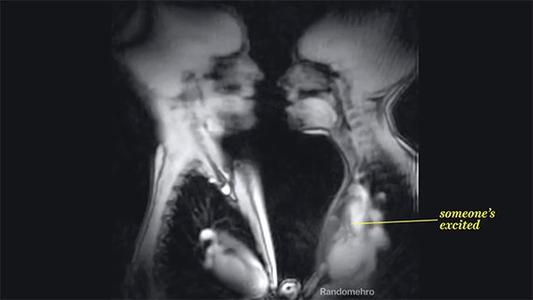

但遗憾的是,一直以来人类对*行为性**的了解十分有限,为了更加深入的了解人类发生*行为性**时身体到底发生了什么变化,在1991年,来自荷兰格罗宁根大学医学部的科学家Weijmar Schultz做了一个这样的实验:

Weijmar Schultz首先通过个人邀请以及当地的一个科学节目进行招募志愿者,最后参与实验的一共有8对夫妇以及3名单身女性,共进行了13项实验,所有参与实验的人员信息会全部进行保密。

利用核磁共振成像技术研究了啪啪过程中女性以及男性的生理反应,并观察了男女私密处在这个过程中的变化,

为了更好地实现整个实验过程,Schultz使用了空间更大的核磁共振设备,设备空间直径达到50cm,在核磁共振成像下,人体内的所有生理变化几乎能够一览无余。